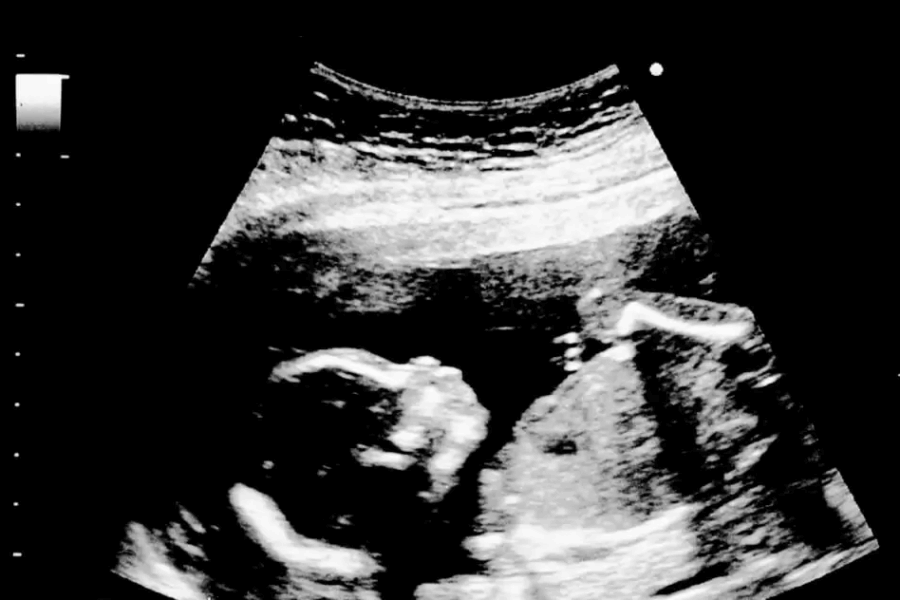

O congelamento de óvulos para mulheres acometidas pela endometriose é indicado especialmente quando os endometriomas estão presentes.

O endometrioma é um cisto benigno. É uma das formas de endometriose que se estabelece quando as lesões acometem os ovários. Tende a se formar próximo ao córtex do ovário, porção do órgão onde está localizada a reserva ovariana, por isso a ameaça à fertilidade feminina é real.

A formação do endometrioma pode prejudicar a reserva ovariana e acarretar perda folicular. Ou seja, o número de óvulos disponíveis diminui, reduzindo também a capacidade de ovulação e as chances de concepção.